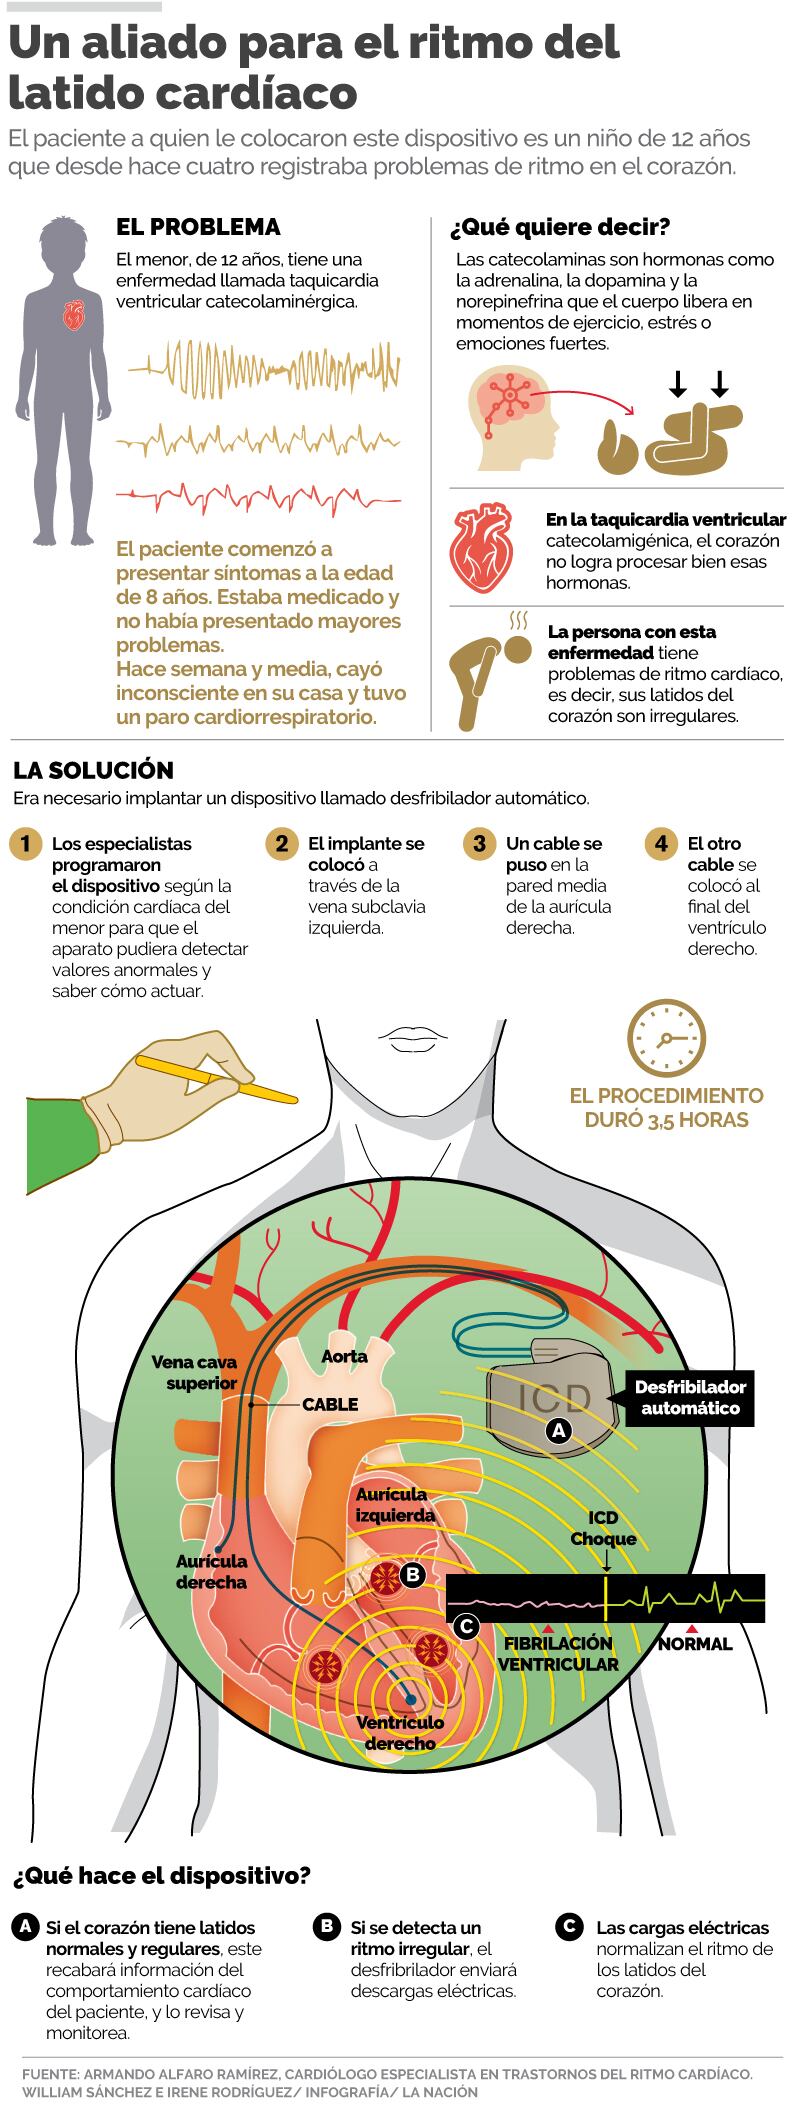

Un menor de 12 años y vecino de Liberia, Guanacaste, comenzó con latidos irregulares en su corazón hace unos cuatro años. El diagnóstico no fue fácil por lo extraña de su enfermedad: taquicardia ventricular catecolaminérgica, un mal que en Costa Rica, en los últimos diez años, solo ha sido detectado a él y a otro menor.

¿En qué consiste esta enfermedad? Para ello, debemos entender primero que son las catecolaminas. Son neurotransmisores u hormonas que el cuerpo libera en diferentes niveles cuando realizamos actividad física o estamos ante situaciones muy emocionantes, como estrés, sorpresa, felicidad, dolor o mucha tristeza. La adrenalina, la dopamina y la noerpirefina son ejemplos de estas sustancias.

En condiciones normales, nuestro corazón puede resistir el aumento de los niveles de estas hormonas, pero las personas con la enfermedad de este menor la liberación de estas sustancias puede afectar el músculo cardíaco provocar arritmias –latidos irregulares–. Algunas personas tienen una condición bastante estable y no requieren mayores controles médicos, pero en algunas puede provocar paros cardiorrespiratorios y conducir a muerte súbita.

La solución no podía hacerse esperar. Cuando el menor estuvo estable y bajo control, con latidos del corazón constantes, fue trasladado en ambulancia hasta el HNN, donde ya sabían los pasos por seguir: la colocación de un dispositivo llamado implante desfibrilador automático, que es capaz de “leer” cuando el menor tiene un ritmo irregular en el corazón y envía descargas eléctricas hasta regularlo.

La parte más difícil del procedimiento no es la colocación del implante, pues este se coloca de manera muy similar a como se hace con un marcapasos. Lo realmente trascendental es programar el aparato para que sepa cuáles son las condiciones “normales” y a partir de cuáles debe descargar y con qué magnitud.

“En cada paciente esa programación es diferente, pues se hace adecuadas a las características que la enfermedad presenta en cada persona”, detalló el especialista.

¿Cómo funciona el dispositivo? Si el corazón del menor no registra un ritmo cardíaco anormal, el aparato está “leyendo” las características de cómo funciona normalmente el corazón, guarda los ritmos y monitorea. Si registra que hay cambios irregulares, envía descargas eléctricas para regular el ritmo. Si no se corrige, está en capacidad de liberar múltiples cargas hasta que se vea corregido.

La vida útil de este aparato es variable y depende de cuántas veces y con cuánta intensidad se produzcan las descargas, pero puede variar de unos cuatro a unos siete años. Después de esto deberá cambiarse.